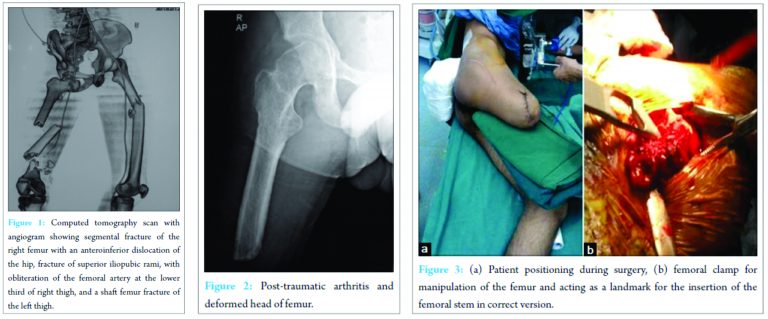

We present a case of 30-year-old male who had a road-traffic accident presenting to us from a remote peripheral center after 24 h of the injury. He sustained bilateral lower limb injuries. On presentation, he was conscious and coherent but in hypovolemic shock. He was managed as per advanced trauma life support guidelines and was made hemodynamically stable. Clinical examination revealed an unreduced right hip dislocation, fracture deformities of both the thighs, an open wound over lower third of right thigh with bruising and swelling, and an open wound over anterior right leg. The right lower limb continued to be cold and clammy after hemodynamic stabilization, with absent distal pulses below the knee. Trauma series X-rays were taken along with a computed tomography angiogram (Fig. 1) which revealed a segmental fracture of the right femur with anteroinferior dislocation of the hip, fracture of superior iliopubic rami, with obliteration of the femoral artery at the distal femur and a shaft femur fracture of the left thigh. After hematological and serological work up and multidisciplinary assessment and keeping in mind the delayed presentation (beyond 24 h), the decision to go for above-knee amputation of right lower limb was taken and the patient was planned for emergency surgery. On exploration, the popliteal artery was seen to be lacerated at multiple points with distal thrombosis and above-knee amputation was carried out. The right hip was impacted in the obturator foramen which could not be reduced by closed attempts, hence required open reduction, done by a posterior approach. The head of the femur had impaction injuries with full thickness cartilage loss in the superolateral region. An external fixator was given to stabilize the left femur fracture, which was later converted to interlocking nailing at 5th postoperative day. The patient had an uneventful recovery and underwent supervised physiotherapy. At 2-month follow-up, when the patient was advised for weight bearing with an above-knee prosthesis for amputated right lower limb along with axillary crutches, he complained of severe pain in the right hip and was unable to weight bear. Further 1 month of non-weight bearing was advised to heal the rami fracture. Radiographs of the right hip at 3-month follow-up showed an evidence of posttraumatic arthritis and deformed head of femur (Fig. 2). To alleviate his painful hip and mobilize the patient, a decision of THR was taken.

The patient was put in a left lateral decubitus position on normal OT table, secured with anterior and posterior supports acting over the pelvis. Prepping and draping of the stump were done. The procedure was carried out through a minimally invasive (MIS) anterolateral approach as these patients have a high propensity for postoperative dislocation during early rehabilitation period with the above-knee orthosis. A 8 cm incision was made starting from trochanteric ridge midway from anterior and posterior trochanteric borders extending around 4 cm proximal to tip of the greater trochanter. Subcutaneous tissue and fascia lata were divided in line of incision. Intermuscular dissection was done digitally between the gluteus medius and tensor fascia lata. Anterior joint capsule was incised in line of femoral neck. Dislocation of the hip and positioning of the femur was aided by that placement of a bone clamp below the lesser trochanteric area for manipulation. The clamp also acted as a landmark for the insertion of the femoral stem in correct version (Fig. 3).

Secondary post traumatic arthritis in an ipsilateral above-knee amputee, especially in a younger individual, poses a catastrophe, both physiologically and psychologically. The incidence of hip osteoarthritis in amputated patients varies from 5% to 61% and in the long term, the risk to develop hip osteoarthritis compared with general population is double in the non-amputated limb and 6 times higher in the amputated limb and above-knee amputation has a greater propensity to develop arthritis than below-knee amputation [4]. Keeping the above consideration in mind, acementless THR was planned. The first 6 weeks post-THR in an amputee patient is critical with respect to standard hip precautions to avoid dislocation, especially while placing and removing their exoprosthesis [5]. Hence, the decision was taken to use a MIS anterolateral approach, which uses the intermuscular interval between the tensor fascia lata and the gluteus medius. It leaves the abductor muscles, the posterior capsule, and the short external rotators intact permitting acceleration of the postoperative rehabilitation with less perioperative complications, especially dislocation [6,7]. We also decided to use large femoral head (36 mm) to minimize chances of dislocation [8,9]. Careful preoperative planning is required, especially preoperative templating using radiographs with appropriate magnification to assess the length of the femoral stump and width of the medullary canal to ensure correct sizing of femoral stem to obtain a good primary stability and osteointegration of the prosthesis. Main challenges faced intraoperatively in such above-knee amputee cases are related to femoral manipulation, dislocation of femoral head, and subsequent relocation and ensuring proper implant positioning due to lack of references such as the knee or the leg axis to obtain appropriate version of the implant. Malpositioning of components is not desirable as it leads to higher risk of dislocation, compromised component survivorship, and altered gait kinematics [10]. To overcome these shortcomings, we used a femoral bone clamp just distal to the lesser trochanter to carry out the femoral manipulations and the lesser trochanter served as a guide for proper femoral anteversion during insertion of the femoral stem. Patients with lower extremity amputations in need of ipsilateral total hip arthroplasty present with additional challenges with regard to their acute postoperative care and need a modified rehabilitation program. Turney et al. demonstrated that below-knee amputees generally gain better mobility than above-knee amputees [11]. Above-knee amputees are prone to develop flexion contracture and prevention of such contractures by focusing on muscle strengthening exercises should be emphasized.